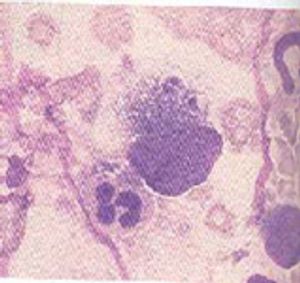

Overview of Protozoans, Giardia, Coccidia, Cryptosporidia, Toxoplasmosis, and more.